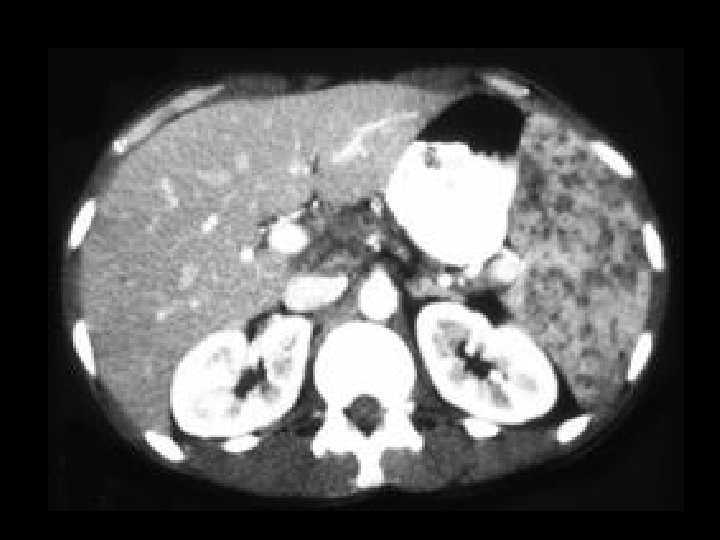

Von-Hippel Lindau • Findings: – Numerous bilateral renal cyst – Solid enhancing right renal mass = RCC • ddx: – NONE! – This is an Aunt Minnie!